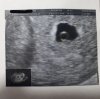

Dziewczyny jestem po wizycie, ta mała bańka ( bo tak wygląda) ma 4 mm jest prawidłowo zagniezdzona, lekarz kazał zrobić 2x bete aby zobaczyć jaki będzie przyrost i na 16 grudnia kolejna wizyta

Super, gratulacje!! :) kiedy miałaś ostatnia miesiączkę? Bo tak zasugerowałam się wymiarami i tym ze masz napisane u góry 5w1d i pomyślałam że chyba nie ma u nas zbyt dużej różnicy. Mi wlasnie z terminu ostatniej miesiączki wychodzić dzisiaj 5+1